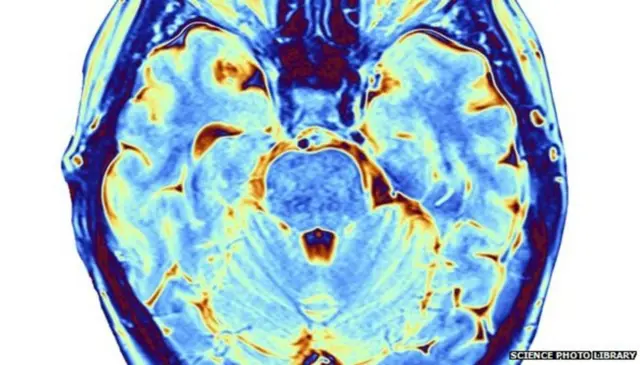

El Daño Cerebral Adquirido (DCA) es una lesión en el cerebro que tiene lugar en personas que nacieron sin ningún tipo de daño. La lesión puede afectar a parte o a la totalidad del encéfalo.

Hay muchas causas posibles, como una caída, un accidente de tráfico, una infección, una falta temporal de oxígeno, un tumor o un derrame.

Una lesión cerebral adquirida puede afectar a la memoria y a los procesos de pensamiento, a la capacidad física, al habla, al acto de tragar y a la psicología y el comportamiento de la persona.

El debut clínico de la lesión cerebral puede manifestarse en cuestión de segundos o después de varios días y los grados de afectación varían mucho de una persona a otra.